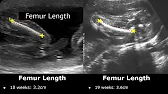

Femur Length Ultrasound Normal Values | Femoral Length Measurements | Fetal Biometric Parameters USG

Dr. Sam’s Imaging Library33

How To Measure Femur Length On Ultrasound | FL Measurement Technique | Fetal Biometric Parameter USG

Dr. Sam’s Imaging Library40